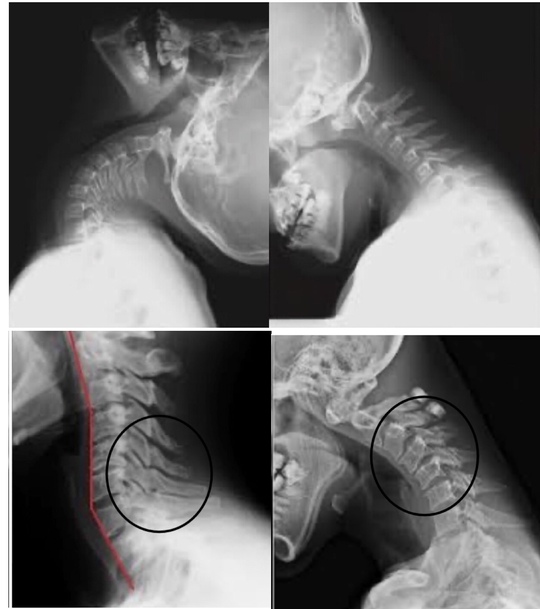

次は首を診てみましょう。

〇の部分が過剰に動くため痛めやすい

上を向いた時と下を向いた時のレントゲン画像の違いがわかると思います。

腰と同様に動きが過剰な場所は痛みが出やすい場所になるし、動かない場所の関節は固まっているため拘縮している場所になる。

上位頸椎には後頭下筋群があり、これが緊張し、凝り固まると頭と上位頸椎が一体化させ、上位頸椎の可動域を失わせます。

上位頸椎の可動性が失われると、下位頸椎が過剰に動くという環境になっていく。

レントゲン写真をみてわかるように、〇の部分で首をメインに動かしています。